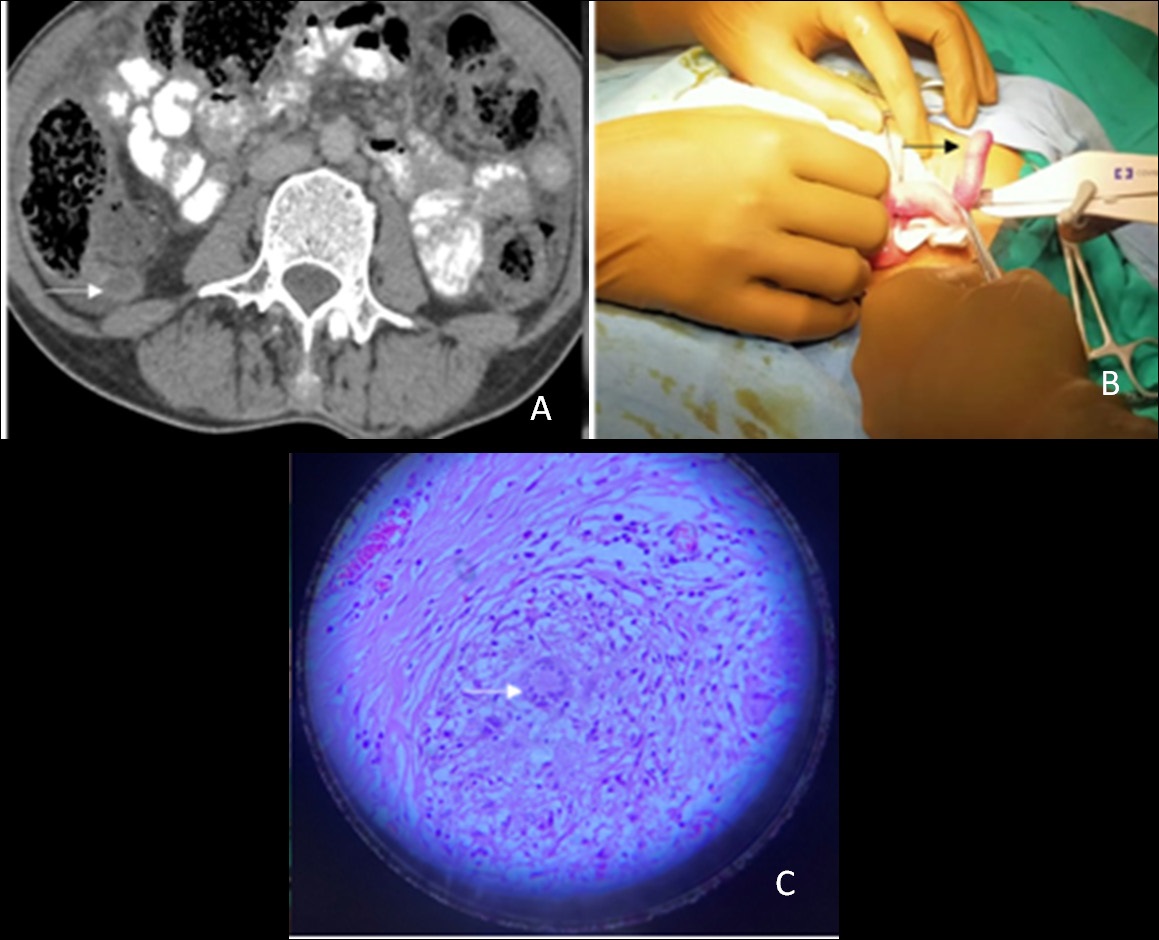

Tubercular appendicitis is usually mistaken as bacterial appendicitis or any other inflammatory disease. The infection can lead to perforation; therefore, it is advisable to remove the appendix in all abdominal tuberculosis patients undergoing surgery for any reason (Figure 6A,6B,6C).

Figure 6: A 37-year-old female presented with severe pain in the right iliac fossa. On clinical examination she had fever and tachycardia with guarding and rigidity in the right iliac fossa. (A) The patient underwent contrast-enhanced computed tomography (CT) scan of the abdomen, which revealed a distended retrocaecal appendix with thick enhancing walls (white arrow) and adjacent fat stranding. (B) The patient underwent appendicectomy and a reddish swollen angry-looking appendix was found intra-operatively (black arrow). The patient had uncomplicated post-operative period. (C) On histopathology, there were multiple granulomatous lesions and areas of caseous necrosis surrounded by Langerhan’s giant cells and epithelioid cells (white arrow). The patient started on anti-tubercular drugs and kept on follow-up. She is doing fine till the last follow up. Acute tubercular appendicitis is very rare condition. A contrast-enhanced CT scan is the ideal imaging modality for the evaluation of such cases.